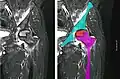

In the early stages, bone scintigraphy and MRI are the preferred diagnostic tools.[18][19]

X-ray images of avascular necrosis in the early stages usually appear normal. In later stages it appears relatively more radio-opaque due to the nearby living bone becoming resorbed secondary to reactive hyperemia.[2] The necrotic bone itself does not show increased radiographic opacity, as dead bone cannot undergo bone resorption which is carried out by living osteoclasts.[2] Late radiographic signs also include a radiolucency area following the collapse of subchondral bone (crescent sign) and ringed regions of radiodensity resulting from saponification and calcification of marrow fat following medullary infarcts.